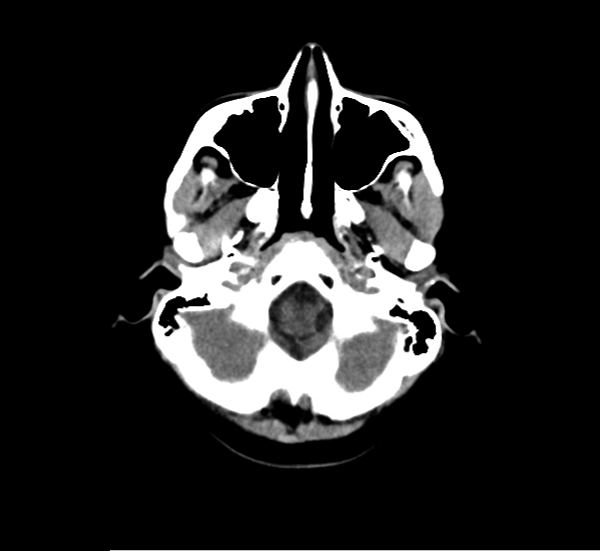

CT Brain Anatomy